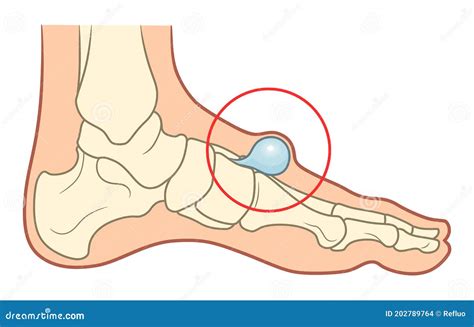

A ganglion synovial cyst foot is essentially a collection of joint fluid that has leaked out of a joint capsule or a tendon sheath. Think of it as a small "bubble" or balloon filled with a clear, jelly-like substance. These cysts can vary significantly in size, ranging from as small as a pea to as large as a golf ball, and they may even fluctuate in size over time.

While they are technically not tumors, they are often referred to as soft tissue masses. They commonly form near the joints of the foot, specifically the top of the foot or around the ankle. Because they are connected to the joint lining or tendon sheath, they move along with the movement of that joint, which can sometimes make them feel more prominent during activity.